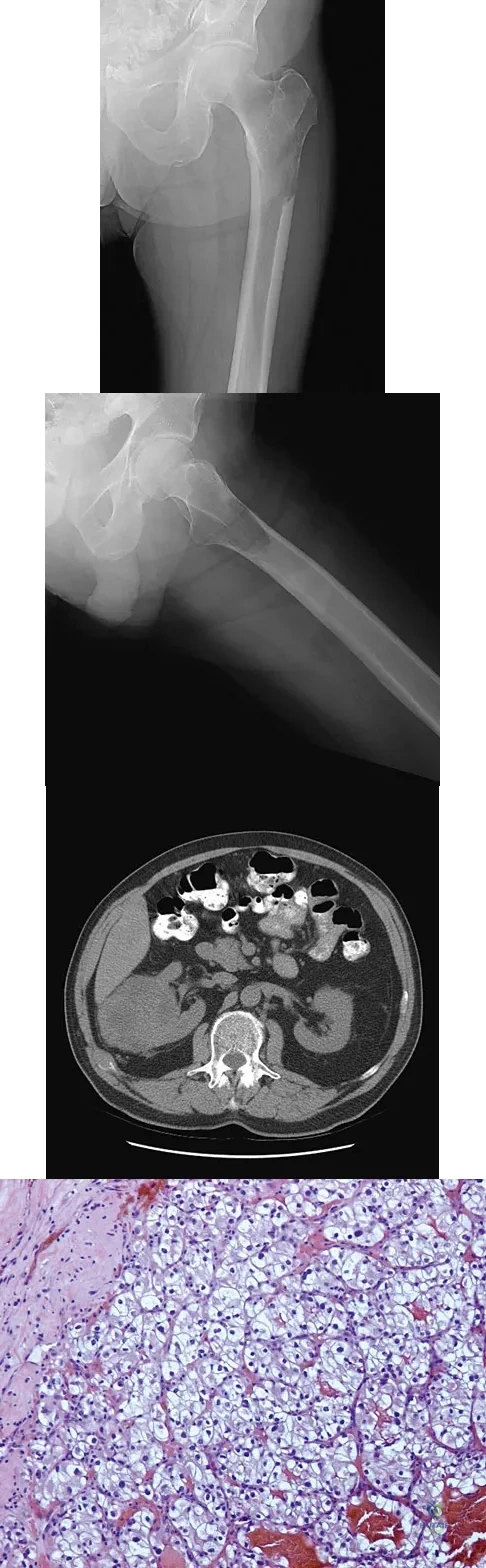

Figures 20a and 20b show the AP and lateral radiographs of a 62-year-old man who has had hip pain for the past 3 weeks. Figure 20c shows a CT scan of the abdomen and pelvis. A needle biopsy specimen is shown in Figure 20d. Preoperative management should include which of the following?

Explanation